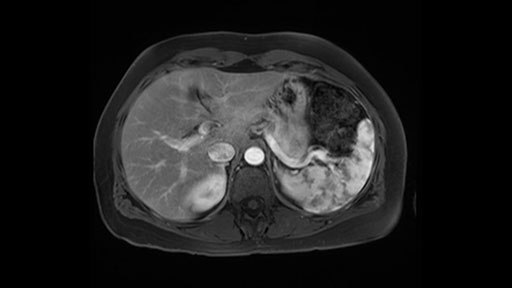

The slowing down moments or considerations that I give when I look at the scan and plan my distal pancreatectomy is how far away the tumor is to the portal vein and do I have to formally create a tunnel behind the pancreas on top of the portal vein or do I have to take the pancreas further to the left of the portal vein or the patient’s left of the portal vein. So here I can see that here is the tumor here. I can see that the tumor is a fair way away to the patient’s right and so I will likely not have to take or create the tunnel formally in this procedure. And that speaks a lot to the resection margins. So its important when you’re doing a distal pancreatectomy or any procedure potentially for oncologic reasons to get clearance of the tumor and to take the tumor kind of intact.

Key features that I look at the imaging are: first I look at the distance between the cyst and the portal vein SMV confluence. So there are guidelines for this, they call the Yonsei guidelines, to decide to do it laparoscopically or open and basically it says that if it’s a cancer, at least a centimeter away from the celiac trunk or the venous confluence. This is a cyst. So maybe you could stretch that a bit, but you don't want to get into trouble there. So for this cyst if you look at it, it's nicely away from the confluence.

So unfortunately I cannot show you a coronal view but you can see it easily on this scan, going down first you see the celiac trunk and you see here, quite a nice distance between the celiac trunk and the beginning of the mucinous cyst. And if you go up here and follow down the portal vein confluence you also see a nice distance there.